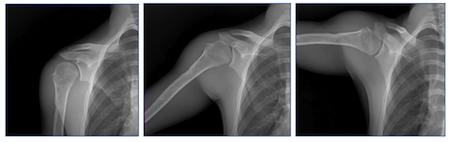

Researchers compared two well-established surgical treatment options to identify which technique most effectively restores native shoulder biomechanics to help inform pre-surgical planning. Using DDR to non-invasively image the shoulder while in motion, they aimed to quantify the scapular contributions to shoulder elevation in patients after anatomic total shoulder arthroplasty and reverse total shoulder arthroplasty.

March 2, 2026 — Emory Healthcare researchers, led by Dr. Eric R. Wagner, recently published a study comparing two well-established treatment options for cuff-intact glenohumeral osteoarthritis in the shoulder. Using Konica Minolta's Dynamic Digital Radiography (DDR), the team evaluated which surgical technique most effectively restores native shoulder biomechanics. The alterations in scapular motion and their clinical significance in patients with glenohumeral osteoarthritis following total shoulder arthroplasty is poorly understood.

Using DDR to non-invasively image the shoulder while in motion, the researchers aimed to quantify the scapular contributions to shoulder elevation in patients after anatomic total shoulder arthroplasty (aTSA) and reverse total shoulder arthroplasty (rTSA). The study is available in the Journal of Shoulder and Elbow Surgery.

DDR is a novel, low-dose X-ray imaging technique available from Konica Minolta Healthcare that captures as series of static images acquired in quick succession, known as a cinegrams, providing an innovative way to obtain detailed images of complex joints like shoulders while in motion. By acquiring a series of images at high speed, DDR generates a cineloop that enables clinicians to visualize anatomical motion over time (cineradiography), enhancing the system’s diagnostic capabilities.